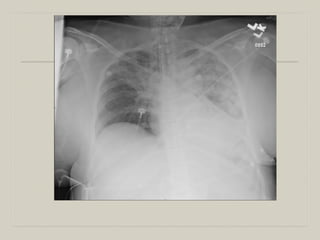

    49-year-old WF h/o bipolar disorder, conversion disorder, found unresponsive at

home. Before intubation in the field, she had a large emesis. She remained

unresponsive and her pupils were dilated up on her initial evaluation according to the

ER physician. In the emergency room, she became hypotensive and received several

boluses of fluid.

    Temp 96.4. BP 74/54 HR 92

    CBC 11.7, 14.8/46, 232

    Chem: 133/3.9, 101/20, 10/0.93, 140

    Lactate 3.7

    ABG: 7.29, 46, 170 on 100% O2

    4 liters of fluid later, SBP 80, HR 80